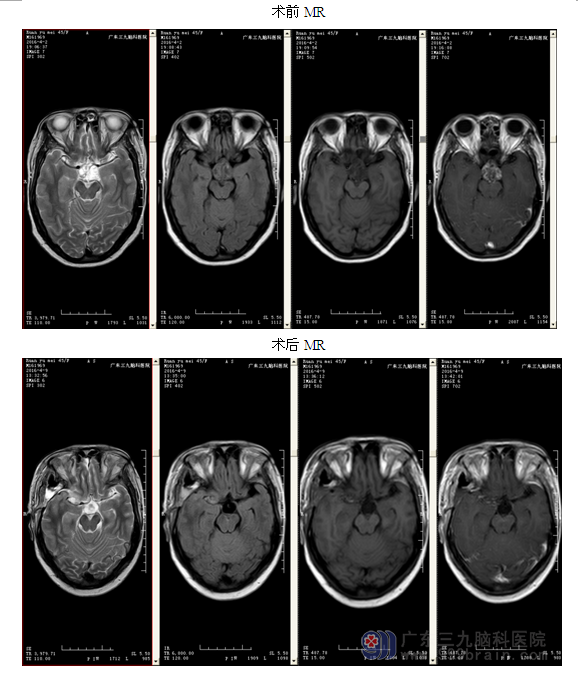

入院后完善相关检查,头颅MRI平扫示:头颅MR提示:鞍区占位性病变,颅咽管瘤复发可能性。查体:右侧视力消失,左侧视力半米数指。诊断:颅咽管瘤术后复发。行全麻下 “颅咽管瘤切除术+ICP探头置入术”,手术由神经外二科主任林涛主刀完成,术程进展顺利,显微镜下将肿瘤全切。病理提示:“鞍区”颅咽管瘤(造釉细胞型)。术后头颅MR提示:颅咽管瘤术占位性病变切除术改变,原病变已全切除。